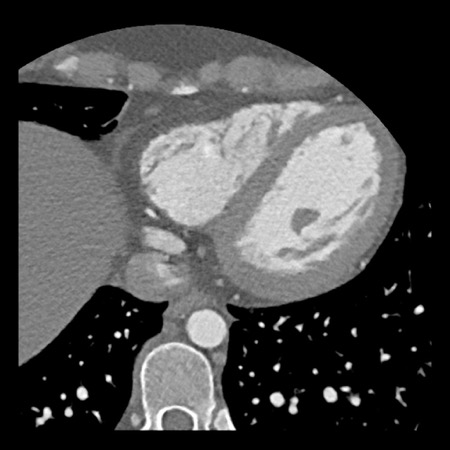

…

Same patient.

A: Curved MPR of the LAD with non-calcified plaque causing moderate (50-69%) stenosis.

B: The so-called “spider-view” (LAO caudal) of the heart with a 70% stenosis in the proximal LAD. Note the presence of SA nodal artery arising from the proximal LCX and coursing to posterior direction.

C: A drug eluting stent (DES) was implanted into the proximal LAD with good results.